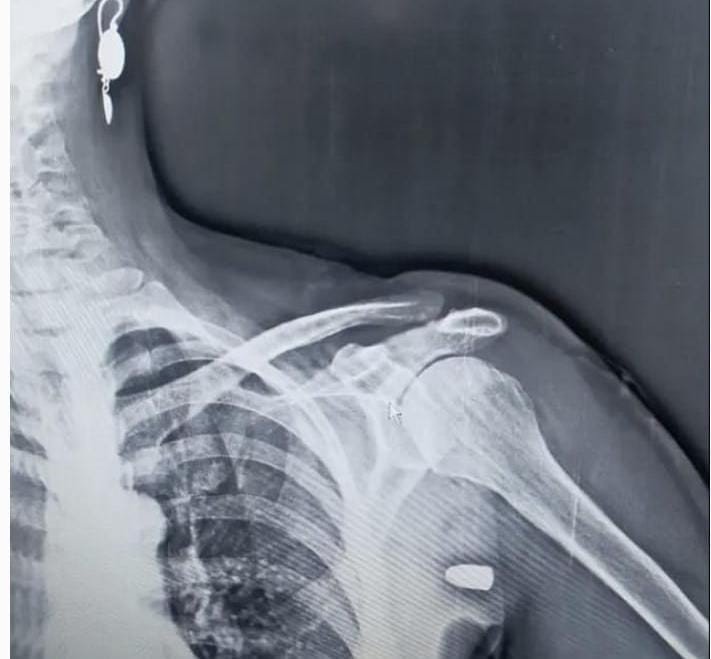

Trabzon'un Tonya ilçesinin Karaağaç Mahallesi yakınlarındaki Hırsafa Yaylası'nda 2022 yılının Kasım ayında ot biçen Asiye İnce (59), sol omuz bölgesinden giren yorgun mermi ile yaralandı. Hastanede tedavi altına alınan İnce mermi çekirdeği ameliyatla çıkartılması sonucu sağlığına kavuştu.